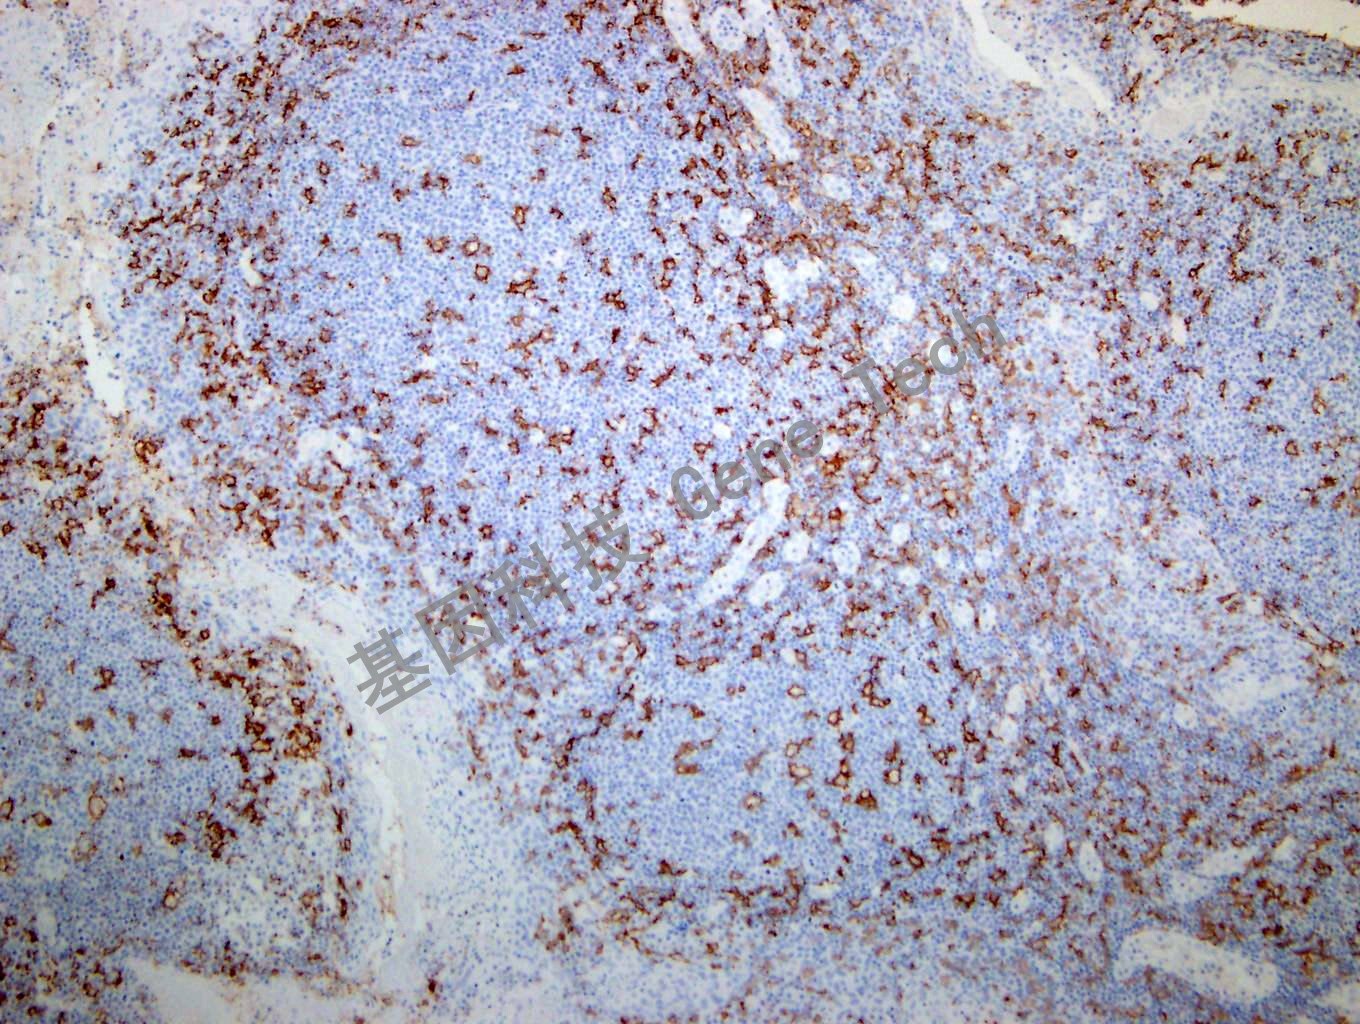

| 簡介:CD11c 是一種I 型跨膜蛋白,屬于整合素α 鏈蛋白家族,又稱IGTAX。可與整合素β2 形成異源二聚體,是白細胞特異的整合素組成形式。同時該二聚體還是非激活補體C3b 的受體4CR4),參與粒單核細胞與活化的內(nèi)皮細胞粘附過程,參與補體包被顆粒物被吞噬清除過程。CD11c 在人體大多數(shù)樹突狀細胞中有高表達,此外在單核細胞、中性粒細胞、巨噬細胞及部分B 細胞中也會有表達。在毛細胞白血病、急性非淋巴細胞白血病和某些B 細胞來源的慢性淋巴細胞把血病中有表達。CD11c 推薦作為抗體組合的一部分,有助于血液系統(tǒng)惡性腫瘤的診斷以及組織內(nèi)巨噬細胞 / 樹突狀細胞的鑒別。 | ||

| 扁桃體石蠟切片,用 CD11c(GT2270)染色,細胞膜陽性,DAB 顯色。(10×) | ||